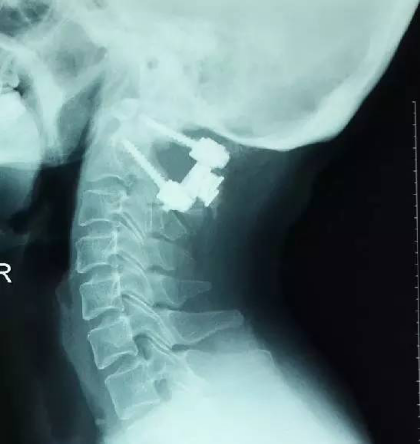

8术后片子

手术前后伸前屈位X光片寰枢椎脱位为可复性(后伸位脱位复位,前屈位寰齿前间隙(ADl)大于5mm)。寰枢椎CT椎弓根发育良好(大于4mm),磁共振脊髓损伤伴椎管狭窄。